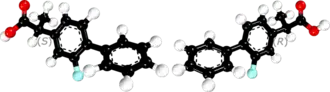

| 3D model (JSmol) | |

| Chirality | Racemic mixture |